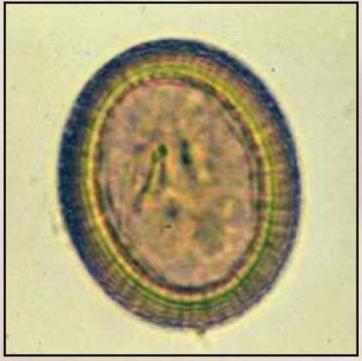

Apacor Barwniki do analiz parazytologicznych

Barwniki do analiz parazytologicznych

Barwnik Fielda A i B:

• Barwienie kałów biegunkowych, aspiratów z dwunastnicy

• Nr kat 1482/1483

Barwnik Giemsa:

• Barwienie kałów nieformowanych, biegunkowych, aspiratów z dwunastnicy

• Nr kat 1484

Barwnik – Płyn Lugola (wodny roztwór):

• Wybarwienie zawartości komórek, na przykład jądra i mas glikogenu, pomagając w tym ich identyfikacji. Dodanie jodu zwiększa refrakcję jądra Endolimax nana, barwi peryferyjną chromatynę jądra gatunków Entamoeba i wykazują dobrze określoną masę glikogenu, która jest cechą torbieli niedojrzałych torbieli E. coli i torbielowatych Iodamoeba butschlii

• Nr kat 1486

Hematoksylina żelazista A i B:

• Wybarwienie na niebiesko z zróżnicowaniem szczegółów jądrowych

• Nr kat 1487/1488

Trichrom – barwnik dla Microsporidia:

• Zarodniki jajowate odbijają światło, ścianki jaskrawe różowo-czerwone. Tło zanieczyszczeń oraz bakterie- zabarwione kontrastowo zielonkawym kolorem

• Nr kat 1489

Trichrom – barwnik dla Protozoa:

• Nr kat 1490

Fuksyna karbolowa (Gram):

• Barwnik używany w technice Grama

• Nr kat 1495

Zieleń malachitowa:

• Zielony barwnik do różnicowania bakterii

• Nr kat 1501

Zmodyfikowany zestaw barwników do met. Cold Kinyoun:

• Komórki kwasowe barwią się na czerwono, tło i pozostałe elementy na niebiesko

• Nr kat 1503